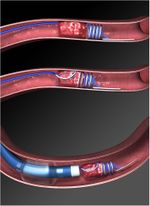

Merci Retriever L5.